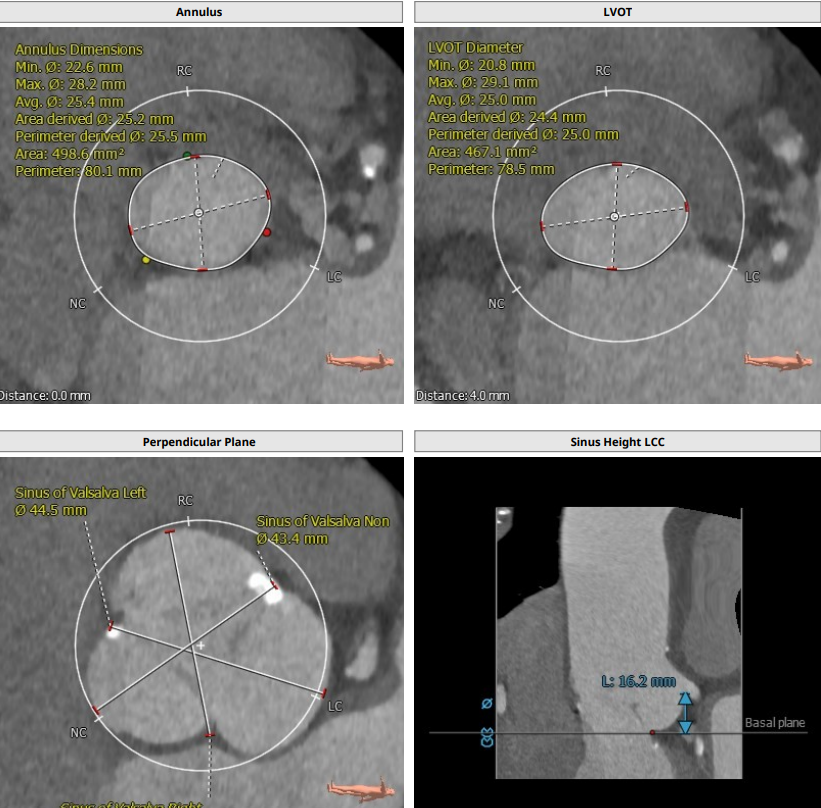

患者男,83岁,解剖为三叶瓣,瓣环径25.5,LVOT25,法式窦结构大,长短颈均超过43,左冠高度16.2,右冠高度18.4,STJ39.9,高度为27.7,升主动脉稍增宽,均径在40.1。

综合整体结构,决定选用VenusA29号瓣膜进行植入,VenusA29号瓣膜29MM的瓣环经相对于25.5的瓣环解剖,25的LVOT有13%以上的oversize,且STJ高度为39.9,升主为40.1,相对于VenusA29号瓣膜最大处44的特点,均可以提供锚定力。

根部解剖: